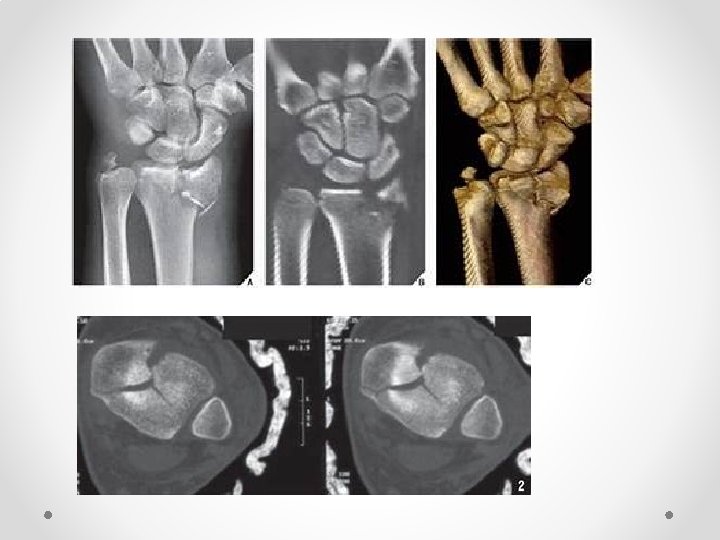

Evaluation of bone injury Initial x-ray analysis includes two views obtained in planes 90º to each other and centered over the zone of injury (Fig 2. 3 -3 a). The remainder of the limb will be examined by xrays, if clinically indicated. To ensure adequate detail, the area of interest should not be covered by dense bandaging or splintage.

• The addition of computed tomography—along with 2 -D and 3 -D reconstruction—provides additional information about the number and position of the articular fragments, the presence of impacted articular segments, the location of metaphyseal fracture lines, and the overall morphology of the injury.